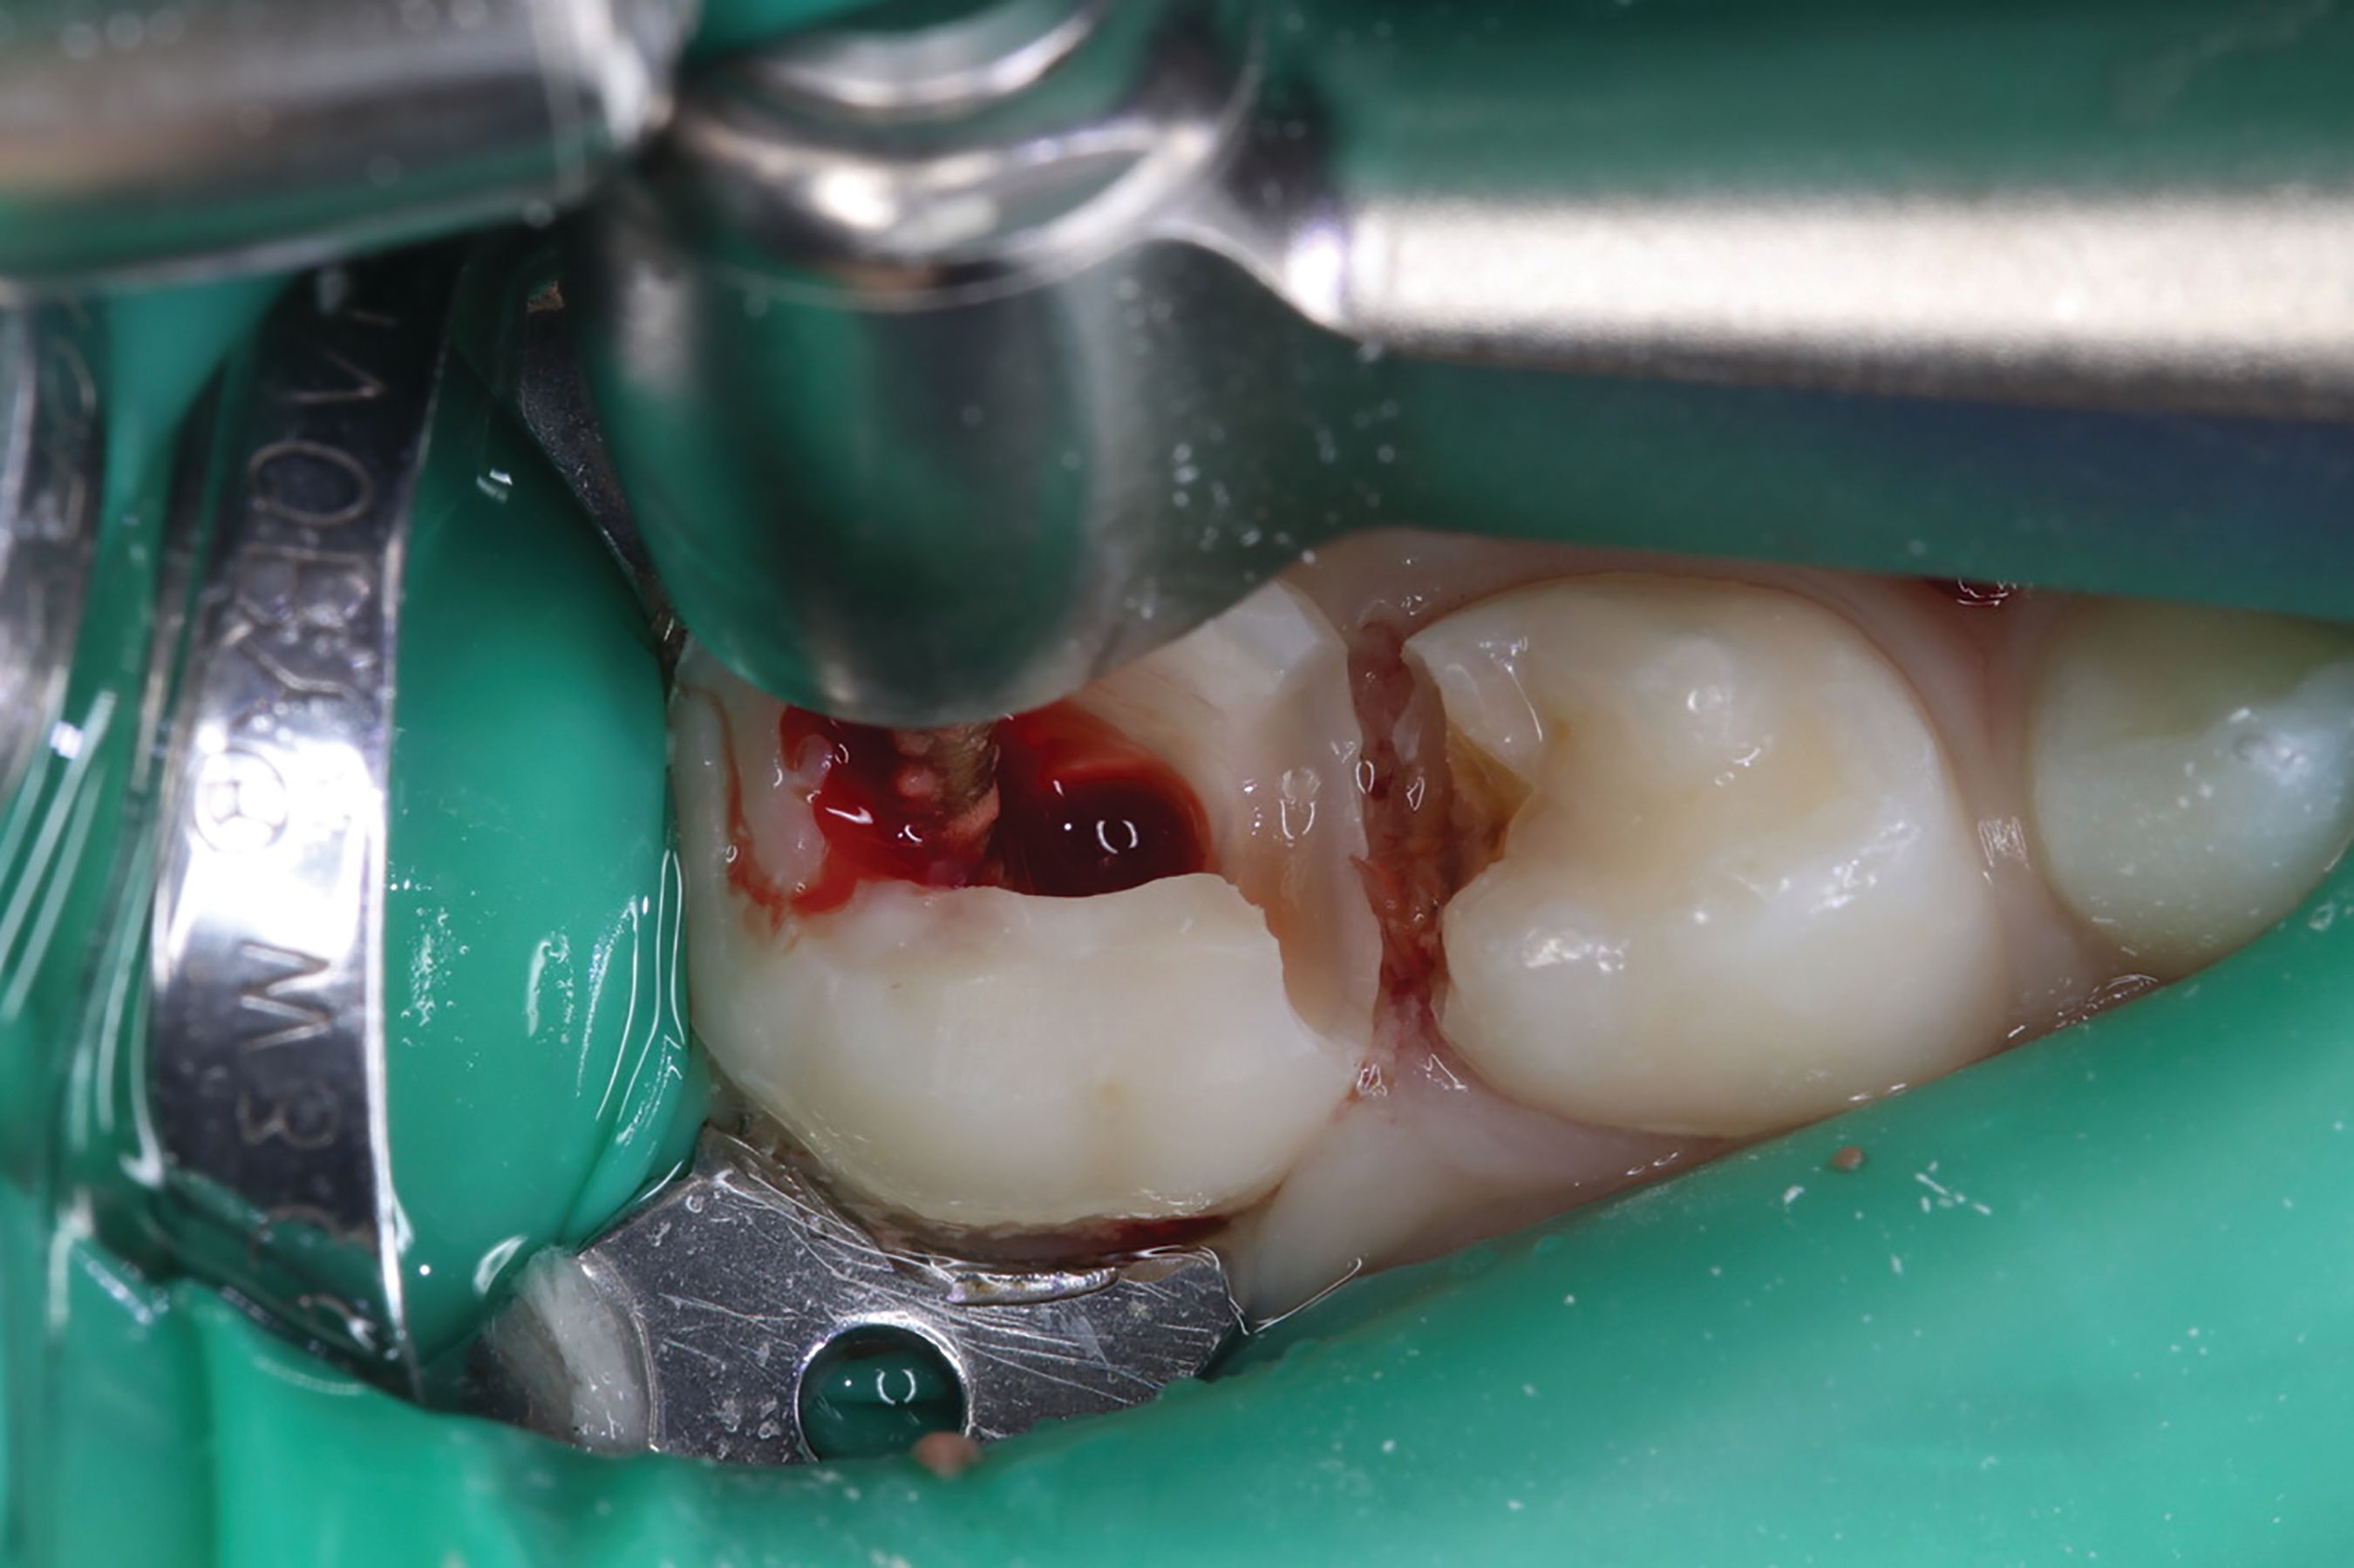

Amputation of coronal pulp chamber to the level of radicular pulp stumps was performed with NSK Dental slow speed large round bur #8, removing coronal pulp tissue with gentle upward motion (Fig. 2). Hemostasis is achieved with a saline-soaked sterile cotton pellet (Figs. 3-4). Figure 5 also illustrates hemostasis.

Fig. 3

Fig. 4

[ Figs. 1-9 ] Pre-operative view-primary second molar requiring pulpotomy procedure (Fig. 1). Amputation of coronal pulp chamber to level of radicular pulp stumps with NSK Dental’s slow speed large round bur #8, removing coronal pulp tissue with gentle upward motion (Fig. 2). Hemostasis achieved with saline-soaked sterile cotton pellet (Figs. 3 & 4). Hemostasis achieved (Fig. 5). Extrusion of TheraCal PT into pulp chamber, being sure to reach base of coronal pulp chamber with material and without voids or bubbles and light cure (Figs. 6 & 7). Cured TheraCal PT (Fig. 8). Full-coverage stainless-steel crown (Fig. 9).